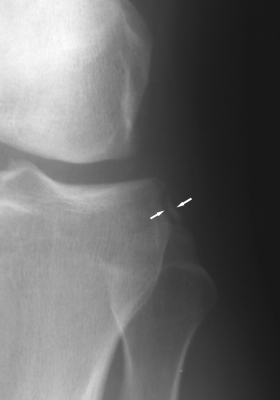

Diagnosis:ACL Tear - Segund fracture Discussion:Frontal radiographs of the knee which reveal a small fleck of bone adjacent to the lateral aspect of the lateral tibial plateau. This "lateral capsular sign" is a simple radiographic finding visible on the routine AP knee x-ray, which indicates severe lateral capsular injury and should alert the examiner to the possibility of ACL tear. The fleck of bone represents an avulsion of the meniscotibial portion of the middle one-third of the lateral capsular ligament. It most commonly implies a disruption of the capsular ligament and the ACL. A-B Radiographs. C. MRI confirms the diagnosis of ACL tear. References: